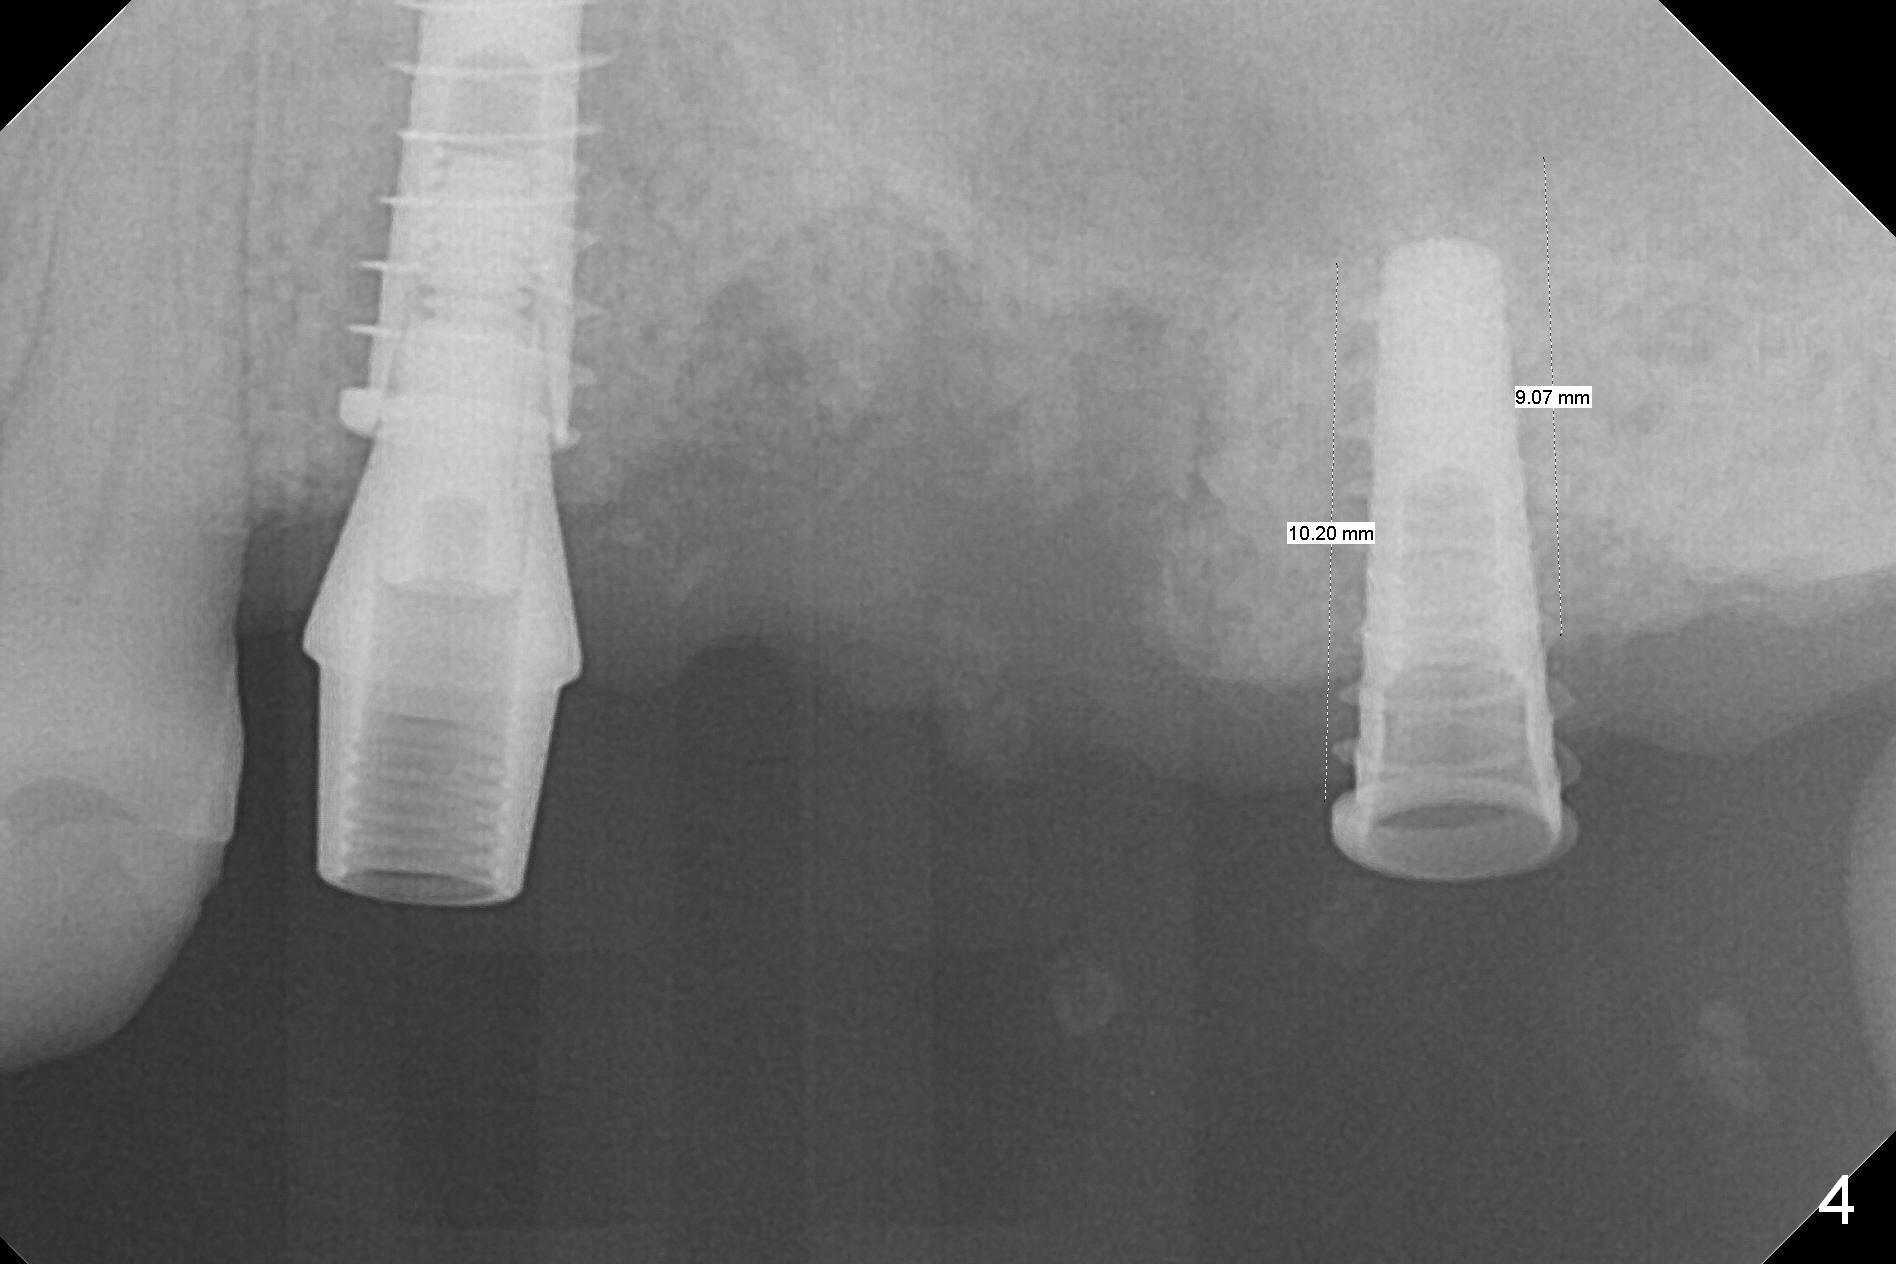

Then 4.3 mm Magic Drill is used at #15. When a 5x9 mm dummy implant is placed mesial to the osteotomy, it slides partially into the palatal socket of #14 (data not shown). When a smaller dummy implant (4.5x11 mm) finds the original osteotomy, the trajectory is acceptable (Fig.4).